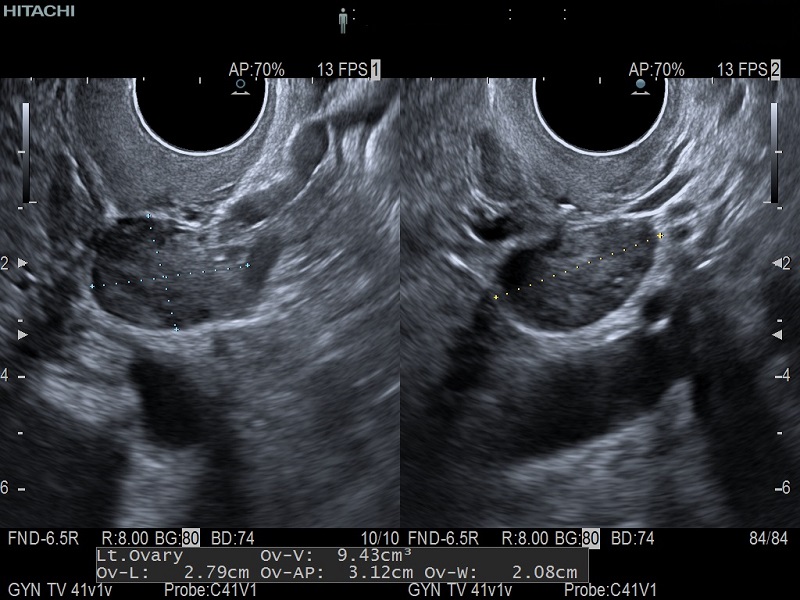

Dormed Hellas AR65 – GYN Dormed Hellas AR65 – OB 2D

Dormed Hellas AR65 – OB 4D Dormed Hellas AR65 – Kidney